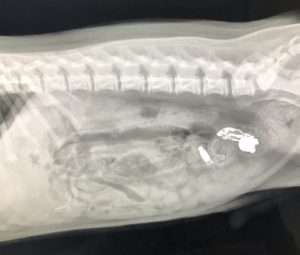

Our experienced veterinary team provides comprehensive medical care for dogs and cats, from routine services to advanced diagnostics, procedures, and treatments.

We are equipped to manage the majority of your pet’s medical and surgical needs right here in our hospital.

What truly sets our advanced care apart is our ability to collaborate directly with multiple board-certified veterinary specialists within our trusted network. When a case would benefit from additional expertise, our veterinarians can consult with in-network specialists. This collaborative approach allows us to deliver a higher level of care while keeping your pet’s treatment as seamless and stress-free as possible.